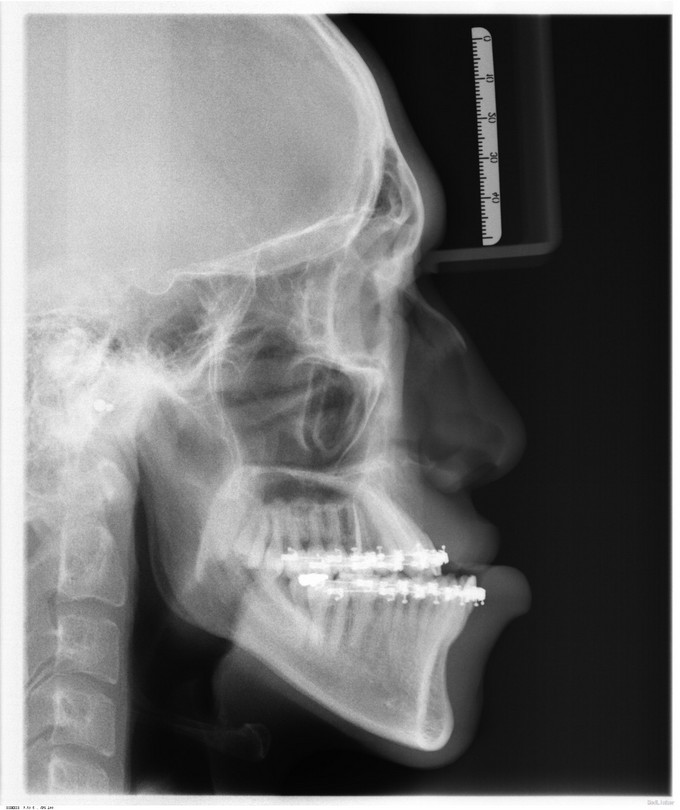

自觉上颌后缩 ,下颌前突数年。

面部发育良好,中线左右对称,上中下比例协调,面下三分一过长前突,颏顶点正中。左侧颞下颌关节无弹响无疼痛动度正常,右侧颞下颌关节开口末期可触及绞索感,无弹响无疼痛动度正常。张口度5.5cm,开口型正常。上下牙弓关系不协调,前牙反牙合后牙近中错牙合,龋齿无,牙周病无。

诊断:1.上颌后缩2.下颌前突,全麻下行上颌LeFortⅠ型截骨前徙术+双侧上颌骨骨内坚固内固定术+双侧下颌骨矢状劈开后退术+去骨皮质术+坚固内固定术+双侧邻近瓣转移修复术。

现患者生命体征平稳,一般情况可,双侧面部轻度肿胀,口内创口缝线固定在位,负压引流管已拔出,咬合可。请示上级医师,同意今日出院